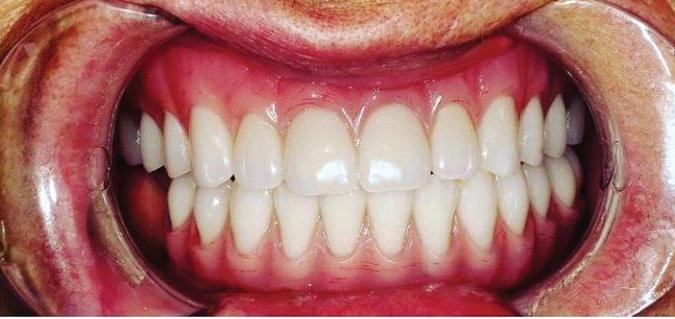

All-On-4 Dental Implants: A Reason To Smile Again

All-on-Four: One Full Arch Of Teeth, Four Dental Implants

To fully understand this remarkable technique for replacing teeth, you should first understand what a dental implant is. An implant is a small titanium screw that fits inside your jawbone and replaces the root-part of a missing tooth. Minor surgery is required to insert the implants. Once the implant is in place, a crown is attached to give you a highly realistic-looking and functional prosthetic tooth.

Here’s where it gets really interesting: You do not need a dental implant for each and every one of your missing teeth. All you need is four precisely placed implants on the top of your mouth, and four on the bottom, to restore your full smile. That’s the beauty of the all-on-four. And because the implant is made of titanium, it has the unique ability to fuse to living bone and function as part of it. So eventually, the dental implant becomes part of the jawbone and serves as a strong, long-lasting foundation for your new teeth.

Besides ensuring that your implants are permanently fixed in place, this bone fusion has another important benefit: it prevents future bone loss in the jaw. This helps to maintain a more youthful facial structure – and better oral health. But perhaps the biggest surprise about the all-on-four is how quickly it can transform your life.

What’s The All-on-Four Dental Implant Procedure Like?

It can be scary to get implants for the first time. Most of that fear is probably due to the uncertainty, so here is the step-by-step process for getting an All-on-Four dental implant.

First, your dentist will want to make sure your comfortable, so either local or general anesthesia will be administered.

Second, the dentist or surgeon will prepare your mouth for the implants, which involves removing your remaining teeth that are failing. They will then remove any diseased or infected tissue from your jaw and gums.

Next, they will begin the implantation process. This means they will insert the titanium screws into your jawbone. Most likely, they will place two implants toward the front of your mouth and two towards the back of your mouth so the “anchors” can evenly bare the force of the denture. After the implants have been placed, they will thoroughly clean the surgical sites and suturing all the